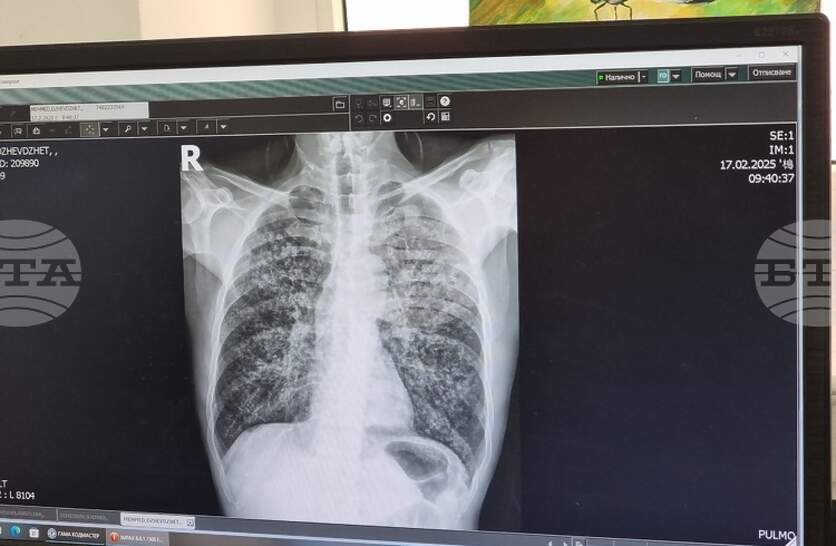

Един новооткрит случай на туберкулоза е регистриран в Ямбол по време на безплатните профилактични прегледи, организирани в периода 23 – 27 март, съобщи директорът на Регионалната здравна инспекция (РЗИ) д-р Радостина Калчева. Болестта е потвърдена при 35-годишен мъж от областния град, който е хоспитализиран в Многопрофилната болница за активно лечение (МБАЛ) „Св. Пантелеймон” в Ямбол. По повод Световния ден за борба с туберкулозата – 24 март, в областната болница се извършваха безплатни прегледи и изследвания за болестта в пневмо-фтизиатричното отделение. През скрининг са минали общо 35 души на възраст между 35 и 70 години, посочи д-р Радостина Калчева. През 2025 г. в област Ямбол са регистрирани 18 случая на туберкулозна инфекция, припомни директорът на РЗИ – Ямбол. Болестта засяга предимно хора с нисък социален и здравен статус, затова в кампанията разчитаме много на здравните медиатори. И през настоящата седмица продължаваме да организираме срещи с акцент върху рисковете от туберкулоза и от морбили, допълни д-р Калчева